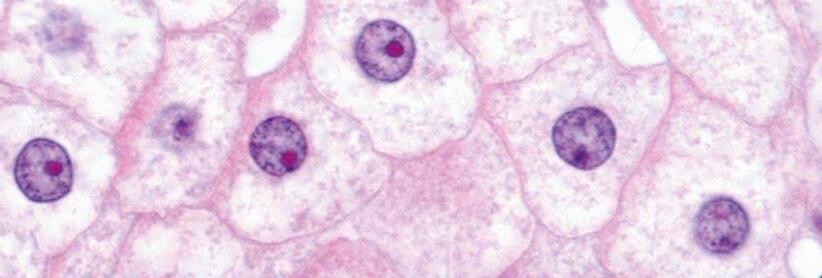

They are secondary metabolites of certain fungi (genera Aspergillus, Penicillium, Fusarium, Alternaria, and Claviceps)[1] and are produced before harvest of grains (fungi as plant pathogens), or during storage (fungi growing saprophytically).

AFs are produced mainly by Aspergillus flavus, A. parasiticus and A. nomius and are detected usually in maize, peanuts and cottonseed.

AFs and, in particular, AFB1 are considered the most potent naturally occurring carcinogens. AFB1 is metabolised predominantly in the liver by a number of cytochrome P450 enzymes, generating several hydroxymetabolites, such as AFM1, AFQ1 and AFP1 and two significantly reactive epoxides, AFB1 exo-8,9-epoxide and AFB1 endo-8,9-epoxide[20-22] .

The exo-epoxide interacts with the guanine part of DNA, resulting in the formation of AFB0-guanine adducts such as AF-N7-Gua which can be used (in urine) as a biomarker of exposure[20,21,23]

Both the endo- and exo-epoxide of AFB1 are toxic and lead to the formation of aflatoxin–albumin (AF-alb) in hepatocytes, which are observable in the sera of exposed animals and humans[20]. These albumin adducts of AFs have been discussed as useful biomarkers of AFs-induced hepatotoxicity[20]

Aspergillus species mainly, and Penicillium species can produce ochratoxins with OTA having major nephrotoxic properties.